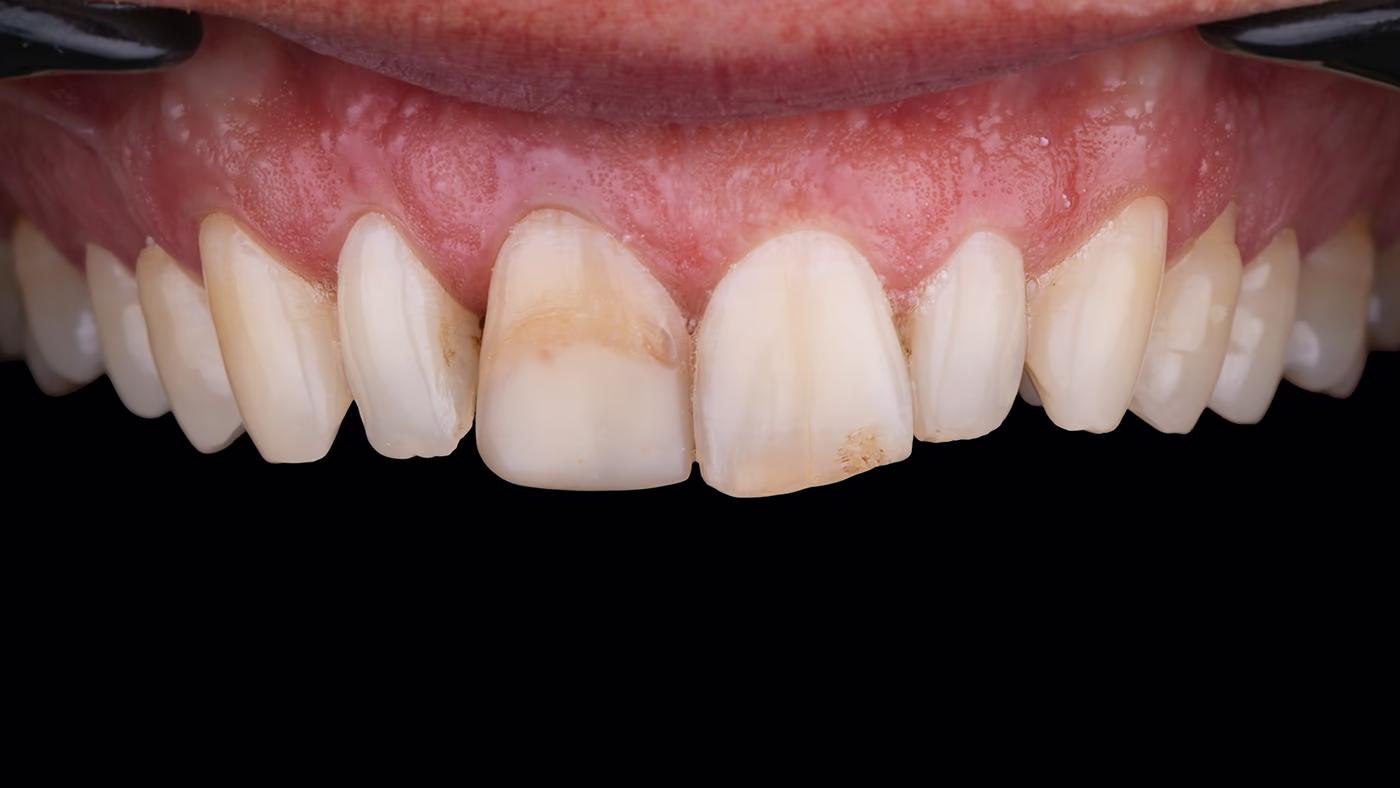

Анамнез.

Пацієнт М., 35 років, звернувся зі скаргами на незадовільний зовнішній вигляд переднього зуба. Його прохання – покращити зовнішній вигляд із мінімальним втручанням.

Об'єктивно.

Зуб 11 із раніше виконаною композитною реставрацією. В анамнезі – ендодонтичне лікування понад 5 років тому. Зуб відновлений із застосуванням скловолоконної штифто вої конструкції та композиту.